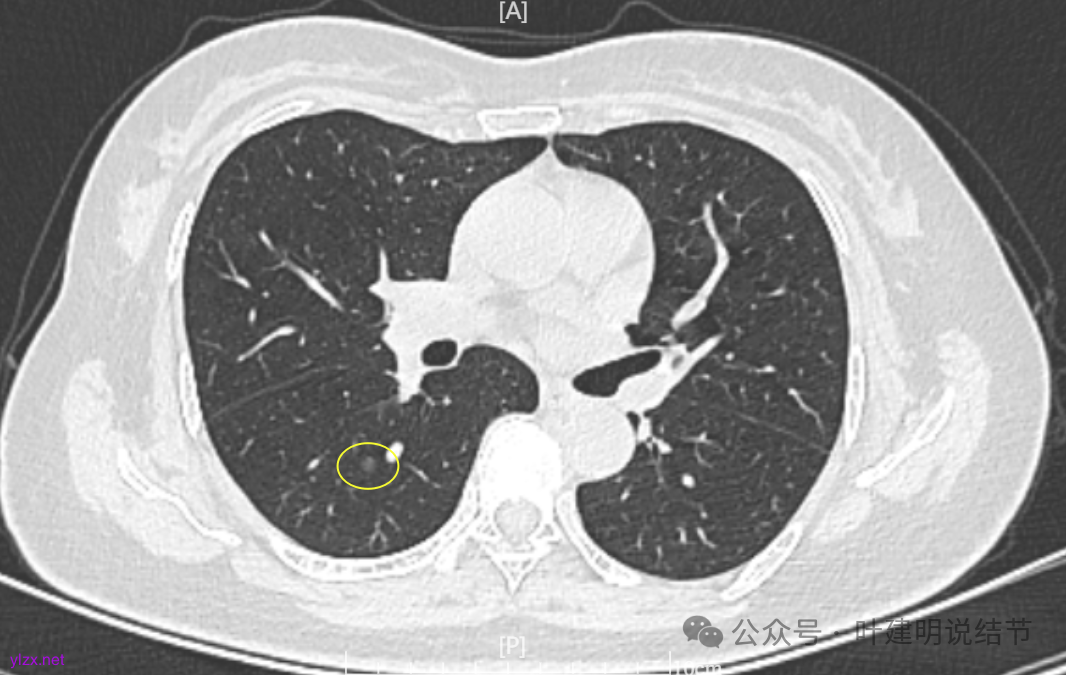

1.判断结节的良恶性。2.下一步的诊疗建议,是要立即切除还可以继续观察?3.是楔切还是段切?

两肺多发结节,持续存在,总体上看,瘤肺边界清,轮廓清楚,主病灶有血管穿行,表面也不平,考虑微浸润性腺癌可能性大,其他2处不典型增生或原位癌可能性大些。总的来说,风险还不大,也不会引起胸痛症状,但因两侧都有,且可能后续均是要手术的,个人觉得左侧病灶可以考虑先切除,因为两个病灶离得不远,总的来说还是靠边缘的,定位后楔形切除能将两处都切了。这样只需再关注右侧的,以后真右侧也要手术,也可拉长两次手术的间隔时间,有利于恢复以及耐受性会好些。两侧同时手术,疼痛、咳嗽、恢复情况容易差些,也容易合并肺炎或其他并发症,安全性差一点的。以上意见供参考!

两肺多发磨玻璃结节,主病灶混合密度且有小血管进入,表面不平有毛刺,考虑微浸润性腺癌或浸润性腺癌可能性大,其余部分考虑原位癌或微浸润性腺癌,部分考虑肺泡上皮增生或不典型增生可能。总体上对比2022年说不上太明显的进展。但对于是否手术来讲,我仍倾向当年的意见,左侧的可以考虑近期亚肺叶(个人倾向楔切)切除,右侧的先随访,以后有进展并风险增加再考虑干预处理。因为要拉长两次手术的间隔,这样对机体的创伤与恢复更加有利一些。若定要仍不开刀,则建议要4-6个月复查,不过个人不太主张过于保守随访,对于像主病灶这种有少许实性成分的,不能保证肯定安全。意见供参考!